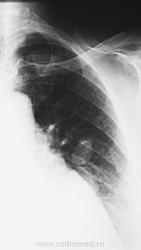

По рентгенографии органов грудной клетки в легких не менее 4 образований... Поскольку живем не в юго-восточной Азии с паразитами, предполагаем в первую очередь метастазы.

Из истории заболевания - оперирована по "женски" чуть больше 1 года назад, получала лучевую терапию....(гинекологи в направлении пишут рак влагалища..